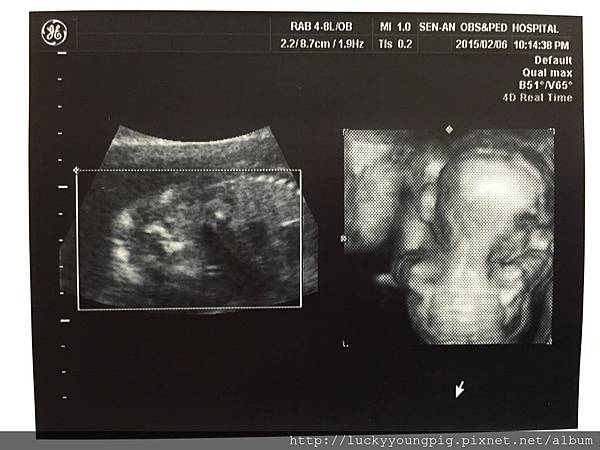

進了診間 醫生請我先照超音波 哇~太吸晴了

是4D的耶 這真的是滿足媽媽的眼慾 哈哈哈~

醫生照的非常仔細 也粉久

寶貝19w2d 頭圍腹圍大小正常 約300g哦~

醫生說 寶貝正在拉耳朵啦 哈哈哈~很調皮哦

醫生說 寶貝沒臍帶繞圍哦

醫生又換個角度照 說百分之百是女生

因為這邊有三個點 嗯~大妹與媽咪我真的看不出來啦 +.+